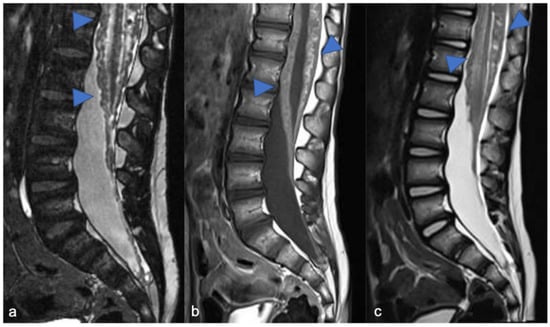

- Thakkar, S.D.; Feigen, U.; Mautner, V.F. Spinal Tumours in Neurofibromatosis type 1: An MRI Study of frequency, multiplicity and variety. Neuroradiology 1999, 41, 625–629. [Google Scholar] [CrossRef] [PubMed]

- Ruggieri, M.; Polizzi, A.; Spalice, A.; Salpietro, V.; Caltabiano, R.; D’Orazi, V.; Pavone, P.; Pirrone, C.; Magro, G.; Platania, N.; et al. The natural history of spinal neurofibromatosis: A Critical review of clinical and genetic features. Clin. Genet. 2015, 87, 401–410. [Google Scholar] [CrossRef]

- Shofty, B.; Barzilai, O.; Khashan, M.; Lidar, Z.; Constantini, S. Spinal manifestations of neurofibromatosis type 1. Childs Nerv. Syst. 2020, 36, 2401–2408. [Google Scholar] [CrossRef] [PubMed]

- Mautner, V.F.; Tatagiba, M.; Lindenau, M.; Fünsterer, C.; Pulst, S.M.; Baser, M.E.; Kluwe, L.; Zanella, F.E. Spinal Tumors in patients with neurofibromatosis type 2: MR imaging study of frequency, multiplicity, and variety. Am. J. Roentgenol. 1995, 165, 951–955. [Google Scholar] [CrossRef]